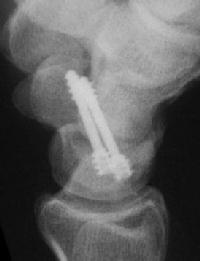

Case 8. Transscaphoid perilunate fracture dislocation...

Click for larger image

Two screws put in dorsally, LT ligament reinforced with a strip of extensor retinaculum left attached to the triquetrium and anchored into the lunate; temporary capitolunate pin.